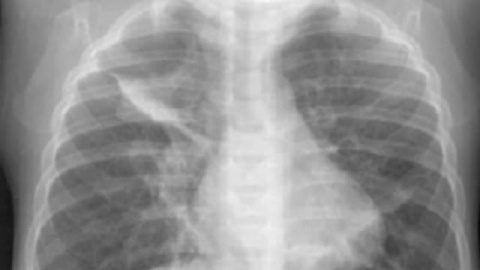

Esta es la historia de tres décadas de lucha. En 1980 Celestino Tolosa ingresó en el hospital con fiebre y tos. Fue diagnosticado de enfermedad pulmonar crónica, pero nunca determinaron qué se lo causó. En 2008 murió durante el trasplante. Y ahí es cuando comienza lo extraordinario de su historia. Su hija nos lo cuenta "él sentía que su cuerpo tenía que ser estudiado". Y así fue porque la última voluntad de Celestino fue que congelaran sus pulmones y es entonces cuando los peritos ven que estaban llenos de amianto. Gracias a esta prueba el Tribunal Superior de Justicia del País Vasco por fin lo reconoce, "hemos confirmado lo que él pensaba, que había enfermado trabajando", relata su hija. La seguridad social asumirá la pensión de viudedad de Kontxi, una mujer que ha sufrido mucho y que está a la espera de recibir la indemnización por parte de la empresa. Esa será la recompensa a la lucha de Celestino, que siempre supo que sus pulmones no mentían.